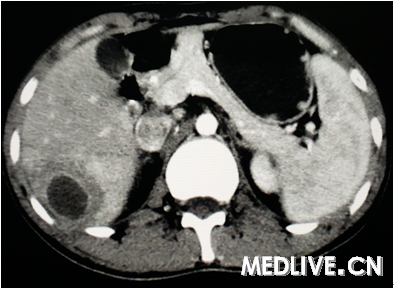

男,26岁,右上腹部疼痛伴畏寒发热3天。

图2为CT增强门脉期,

右上腹痛伴畏寒发热提示有感染存在,CT为囊性病变,动脉期囊腔周围有水肿,静脉期囊腔边缘增强,囊内无增强排除血管瘤;囊内无子囊,无分隔可排除肝包虫感染。最终诊断为肝脓肿。

诊断:肝脓肿。 依据:发热,畏寒考虑感染性疾病,患者右上腹疼,上腹部CT肝右叶可见空腔,周围水肿带,增强可见强化,符合肝脓肿影像。 鉴别:肝囊肿并感染,肝结核。

上腹痛伴畏寒发热提示有感染存在,排除肝囊肿;CT示球形囊性病变,动脉期囊腔周围有水肿,静脉期囊腔边缘增强,囊内无增强排除血管瘤;囊内无子囊,无分隔可排除肝包虫感染。诊断考虑肝脓肿。

CT可见肝内囊性病变,边界清,囊内呈液性暗区(无增强),无分隔,囊腔周围有水肿,综合上述CT表现诊断为肝脓肿。